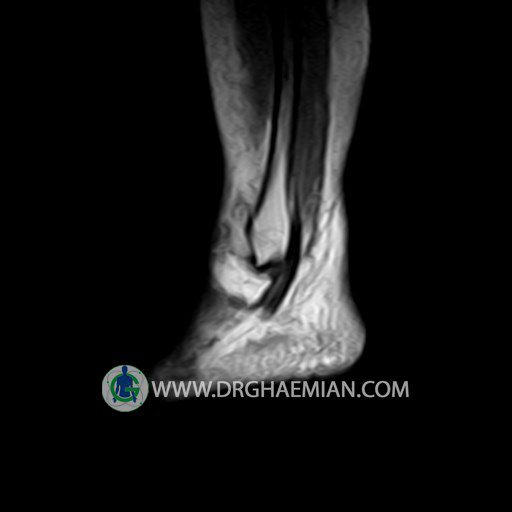

پزشکان اغلب از تصویربرداری ام آر آی برای تشخیص و درمان عارضه های پزشکی که فقط با استفاده از اشعه ایکس یا میدان مغناطیسی و امواج رادیویی قابل مشاهده است، استفاده می کنند. دستگاه ام آر آی تصاویر دقیق از ساختار های داخلی بدن ایجاد می کند. در این کیس تورم مچ پا بیمار مشاهده می شود.

Technique: Sagittal T1, T2 , Axial GE , coronal & sagital fatsat .